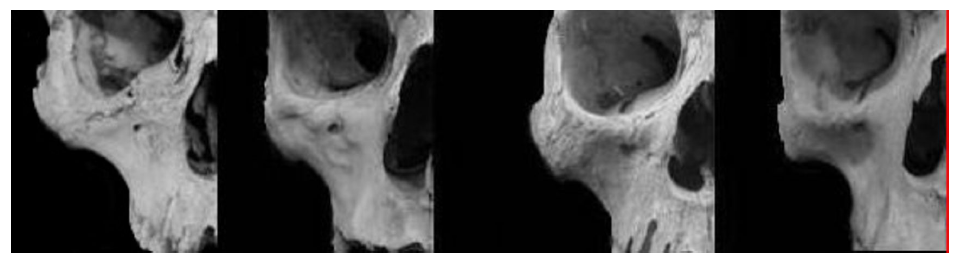

I’ve seen on looksmaxx gg or something that this is the guy who got the lf2 from giant and those are the after results. The lf2 dude was also black and has this type of hair so yh prob was him. But even from 3/4 profile he doesn’t rlly look that forward grown tbh especially his maxilla

morph

morph